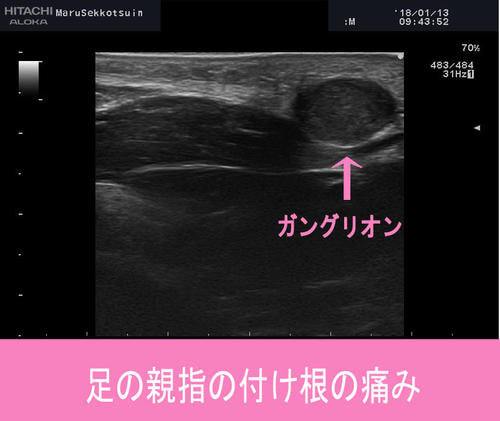

ランニングしていたら"足の親指の付根が痛くなってきた、、、"と御来院。

足の母趾球付近の痛みを訴えられており、

外反母趾でしょうか??種子骨障害でしょうか??

しっかりと問診、視診、触診を行ったところ、

母趾球の下あたりに腫瘤を触知。

そこで登場「超音波画像診断装置」

しっかりと腫瘤「ガングリオン」を確認できました。

ガングリオンは関節包や腱鞘の部分から発生する、

中にゼリー状の物質が詰まった腫瘤。